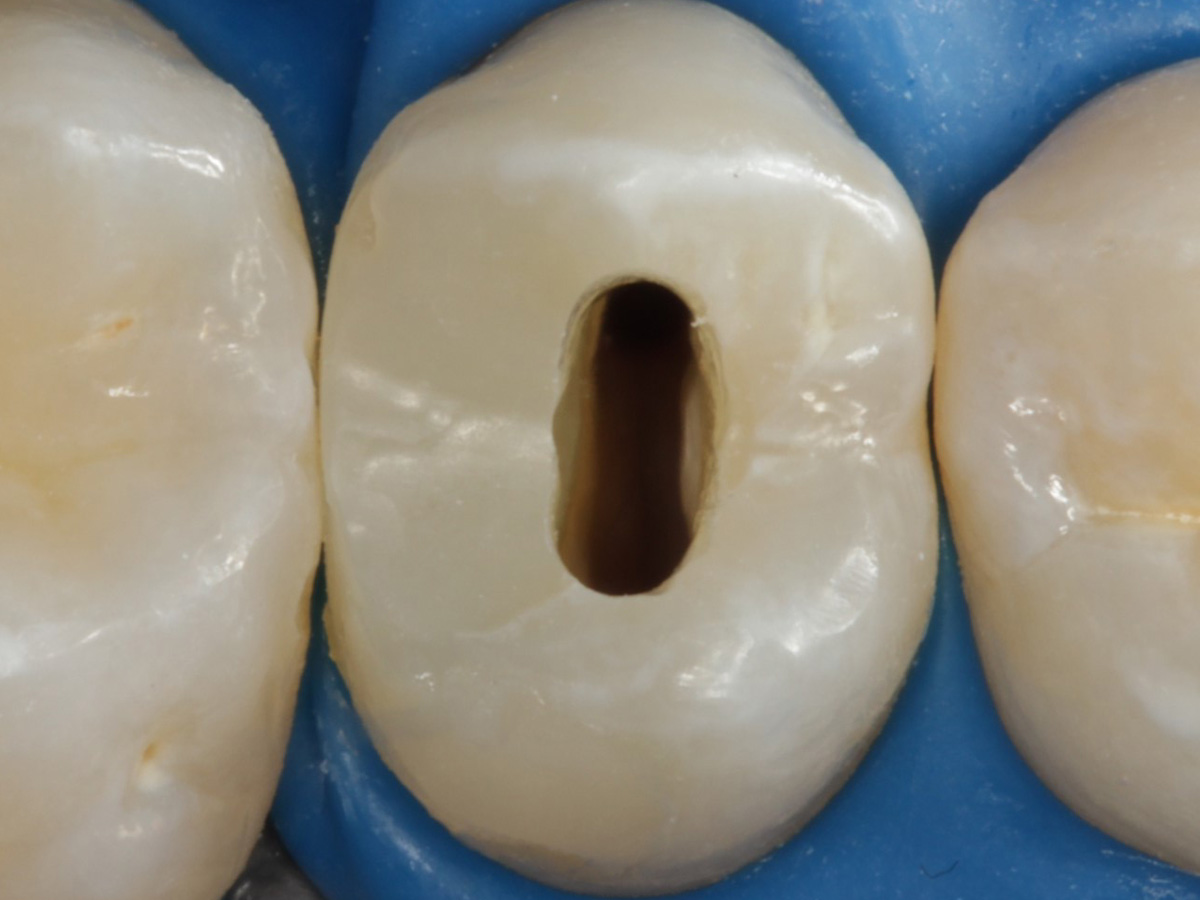

Abbildung 5

Height Indicator vor Auswahl der passenden Evolve Matrize nach Defektdarstellung, Kariesexcavation, Vitalexstirpation